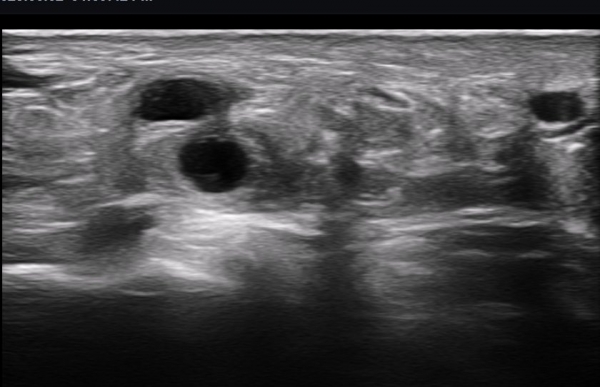

ÃÊÀ½ÆÄ ¼Ò°ß : ºñº¹½Å°æ Ⱦ´Ü¸é°Ë»ç¿¡¼­(»çÁø 1~13) ºñº¹½Å°æÀÇ Àú¿¡ÄÚ ºÎÁ¾°ú ´Üºñ°ñ°Ç³» ³¶Á¾¼º º´º¯ÀÌ °üÂûµÈ´Ù.